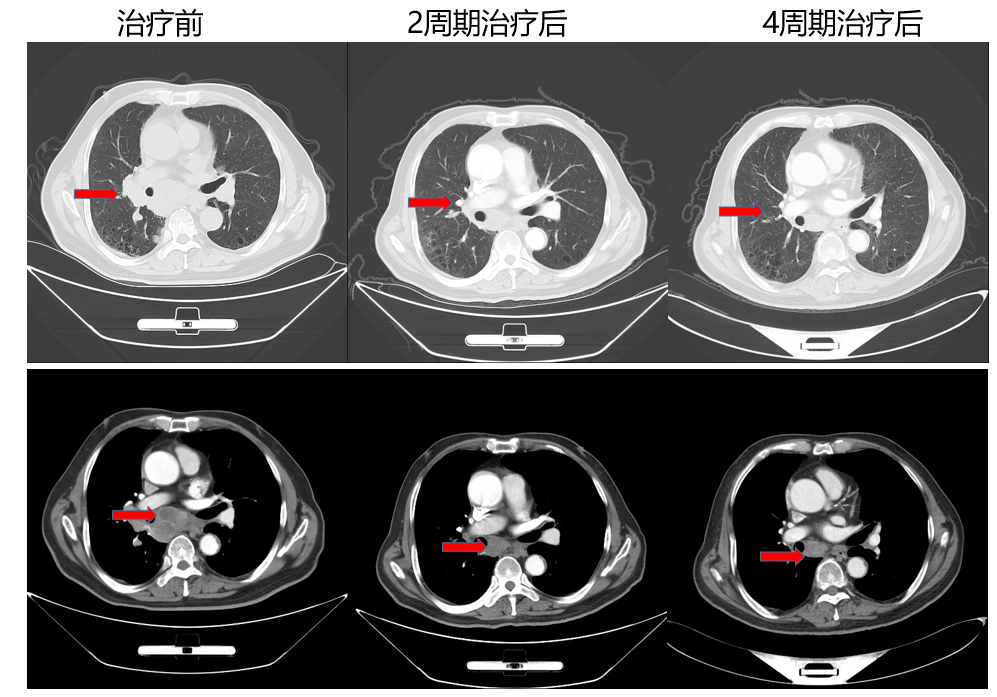

以下面这一例获得治疗的患者为例,患者72,男性,CT检查:1.右肺占位,考虑肺癌并肺内、双肺门及纵隔淋巴结转移;双侧胸膜增厚;双肺气肿;双侧肾上腺区结节,考虑转移;胰腺多发占位,考虑转移瘤;2.胆系梗阻性扩张;脾大,副脾;左肾囊肿;3.考虑脑萎缩;4.双肺气肿。5.细胞室检查 EBUS,考虑小细胞癌,6.NM ECT,全身诸骨未见明显异常。7.颅脑MR未见明显异常。患者诊断为小细胞癌 cTxN3M1c,Ⅳb期,入我科后行阿替利珠单抗 1200 mg+依托泊苷 100mg/m2 +卡铂(AUC=5)方案,经过4周期治疗后,可以明显看到肿瘤的缩小。随着治疗时间的延长,我们期待能够积累到足够多的真实世界数据,验证IMpower133的长生存结果。